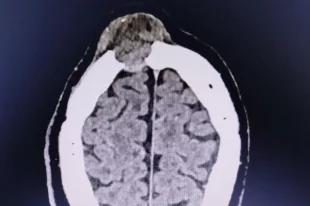

В Ижевске спасли мужчину с опасной опухолью, которая выглядела как шишка

Когда пациент обратился в больницу, опухоль уже разрушала лобную кость.